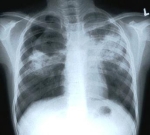

Здравствуйте.Две недели назад при профосмотре обнаружили на рентгене очаговые тени в верхней доле правого легкого.Лечили 7дней от пневмонии с помощью амоксиклава.Как показал контрольный рентген,на обзорном снимке-без динамики,но на срезе топографии,как сказал врач,динамика видна и о Ань хорошая.Однако,фтизиатр поставила диагноз очаговый туберкулез верхней доли правого легкого в фазе инфильтрации.бк(-).Скажите пожалуйста,может ли врач просто перестраховаться и назначить противотуберкулезные п

аппараты,чтоб обезопасить и себя и меня.Анамнез:год назад переболела неспицифическим гриппом(тогда была эпидемия свиного гриппа) в течение двух недель,полгода назад отдыхала в экзотическом Тайланде,отравлений не было,хроническим заболеваем легких не болею,симптоматика отсутствует,работаю в химической лаборатории без респиратора с токсическими аминами,гидразинами.Возможно ли изменение под действием паров химии?Необходимо ли сделать компьютерную томограмму легких для уточнения дигноза.

Здравствуйте Мария, такой сценарий с парами, не возможен, Ваш врач фтизиатр абсолютно прав, следуйте его дальнейшим рекомендациям, повода сомневаться нет.